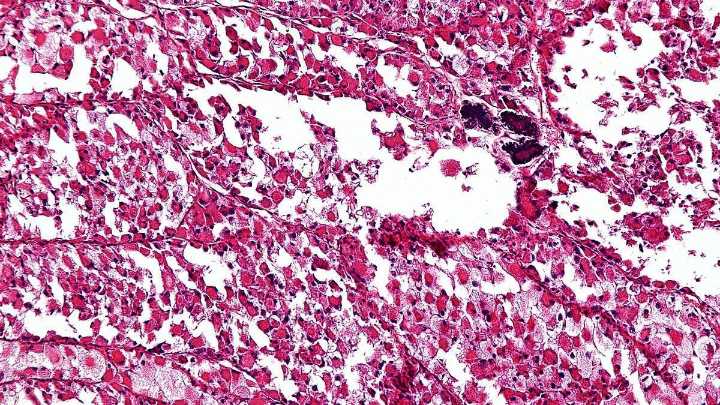

El sarcoma es un tipo de cáncer poco frecuente e histológicamente heterogéneo, ya que puede afectar a personas de cualquier edad. Representan el 1 % de todos los tumores en adultos y el 20 % en niños y adolescentes.

Su frecuencia es excepcional , diagnosticándose entre cuatro y cinco casos por cada 100.000 habitantes al año. Afecta tanto a huesos como a tejidos blandos y hay más de 75 subtipos, que, a su vez, se dividen en sarcomas de partes blandas, suponiendo el 85 %, y óseos, que representan el 15 %.